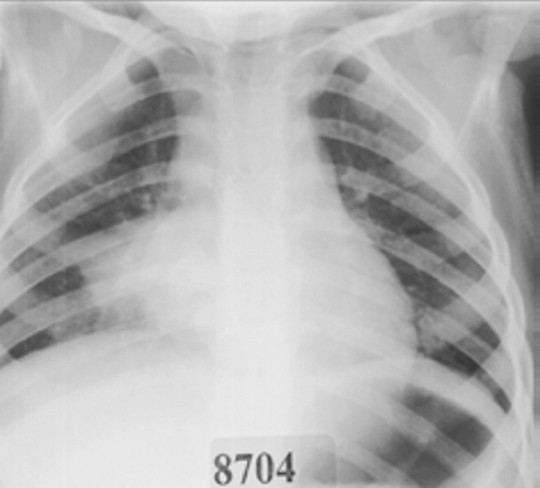

For this type of pneumonia performing a chest x-ray on the. Chest x-rays can reveal areas of opacity seen as white which represent consolidation. In complicated cases of pneumonia perform chest radiography 6 weeks after treatment to verify resolution of the pneumonia and to screen for any underlying predisposing.

Baby chest x ray pneumonia Thursday March 24 2022 Respiratory syncytial virus or RSV most commonly seen in children under age 5 Parainfluenza virus. Pneumonia is not always seen on x-rays either because the disease is only in its initial stages or because it involves a part of the lung not easily seen by x-ray. An important test for making a diagnosis of pneumonia is a chest x-ray.

This chest X-ray shows an area of lung inflammation indicating the presence of pneumonia. However chest X-ray examinations for pneumonia detection are prone to subjective variability 2 3. Please see disclaimer on my website.

The study included 167 children aged more than 12 months. Although the chest x. A chest X-ray is often used to diagnose pneumonia.